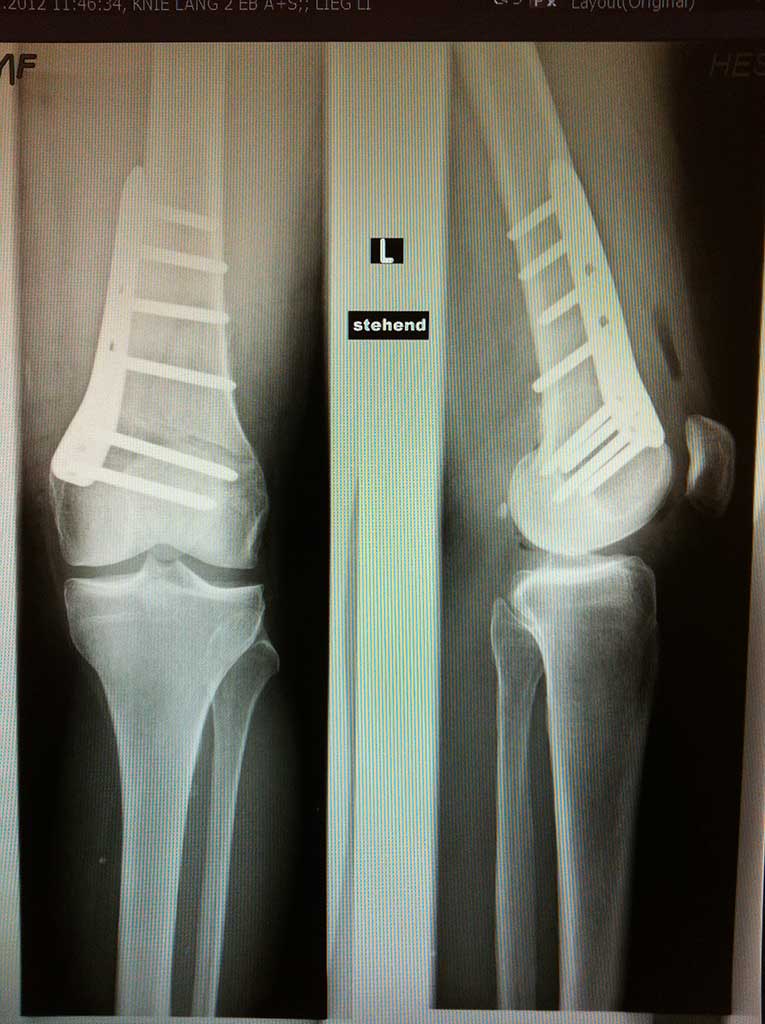

Umstellungsosteotomie Knie DonauwörthKniegelenerhalt bei Arthrose - Umstellungsosteotomie

In der Orthopädie Maximilium Donauwörth steht Ihnen ein einzigartiges Therapiekonzept zum Kniegelenkerhalt bei Arthrose zur Verfügung. Unsere langjährige Erfahrung, Expertise mit dieser Behandlung und jährliche Zahlen von durch einen Operateur durchgeführten Operationen dieser Art (250 - 300 pro Jahr) sind weltweit nur selten zu finden.

Durch dieses minimal invasives OP Verfahren, welches kniegelenksnah entweder am unteren Oberschenkelknochen oder unterhalb des Schienbeinkopfes durchgeführt wird, ändert die s.g. mechanische Beinachse und so kommt es nachhaltig zu einer bis 70% Druckentlastung des durch die Arthrose betroffenen Gelenkbereiches und somit einer wesentlichen Schmerzlinderung, wenn nicht Schmerzfreiheit.

Der Eingriff wird ausschließlich unter stationären Bedingungen entweder in Vollnarkose oder Spinalanästhesie durchgeführt. Die Operation wird durch einen zwischen 5-9cm langen Hautschnitt an dem kniegelenksnahen Knochen durchgeführt, an dem sich der mehr oder wenig ausgeprägte Beinachsenfehler befindet. Häufigerer erfolgt die Osteotomie (= Durchtrennen vom Knochen) unterhalb des Schienbeinkopfes, seltener dann am unteren Oberschenkelknochen. Dies halt allerdings keinen Einfluss auf die Scherzhaftigkeit der Operation, bzw. ihrer Nachbehandlung. Je nach Schwergrad der Arthrose wird des "O" oder "X" Bein in die Gerade umgestellt oder leicht (um wenige Grad) überkorrigiert, damit eine relevante Entlastung erreicht werden könnte.

Die neue Stellung wird mit einer kleinen, extrem stabilen Platte und Schrauben befestigt.

Die Operation dauert zwischen 40 - 70 Minuten, und in unseren Händen wird sie falls notwendig nicht selten mit einem arthroskopischen knorpelwiederherstellenden Eingriff im Knie oder Kreuzbandersatz kombiniert. Dadurch bleibt dem Patienten eine zweite Operation bzw. bis zu 3 Monaten extra Ausfall erspart!

Wie sieht die Nachbehandlung aus ?

Der stationärer Aufenthalt beträgt 4 Tage. Patient darf ab dem 1. postop. Tag mit dem Knie frei bewegen, trägt keine Orthese oder Gips. Die ersten 14 Tage empfehlen wir eine Teilbelastung, welche ab der 3. Wochen in eine schmerzadaptierte Vollbelastung übergeht, so dass unsere Patienten im Durchschnitt 3-5 Wochen postoperativ an Krücken mobilisiert werden. Postoperativ wird Physiotherapie mit ggf. Lymphdrainagen verordnet.

Die vorherigen chronischen Knieschmerzen sind innerhalb der ersten Wochen nach der Umstellung so gut wie weg, dem Patienten bleiben zirka 2-3 Monate Restbeschwerden im OP Bereich.

Die Platte mit Schrauben kann (muss nicht !!!) in 12-16 Monaten innerhalb eines kurzen ambulanten Eingriffes entfernt werden.

Beruflicher Ausfall beträgt zwischen 6-12 Wochen je nach körperlicher Belastung.

Einer der aktuellsten und umfangreichsten Studien an Patienten nach diesem Eingriff konnte zeigen, dass 80-90 % der Patienten waren 10 Jahre nach der Osteotomie (Umstellung) auch mit ausgeprägter Arthrose ohne weiteren Eingriff am Knie mit Ergebnis der Operation sehr zufrieden. Und für die Fälle, wo später (nach 10-15 Jahren) doch durch fortschreiten der Arthrose ein Gelenkersatz empfohlen wird, ist dieser problemlos möglich. Also die Umstellung schließt einen späteren Gelenkersatz nicht aus.